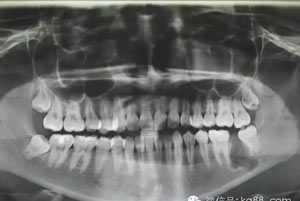

圖1.術(shù)前患者的全景片影像檢查情況:37未萌出,牙冠周圍有囊性陰影,牙根接近下頜骨皮質(zhì)骨邊緣。